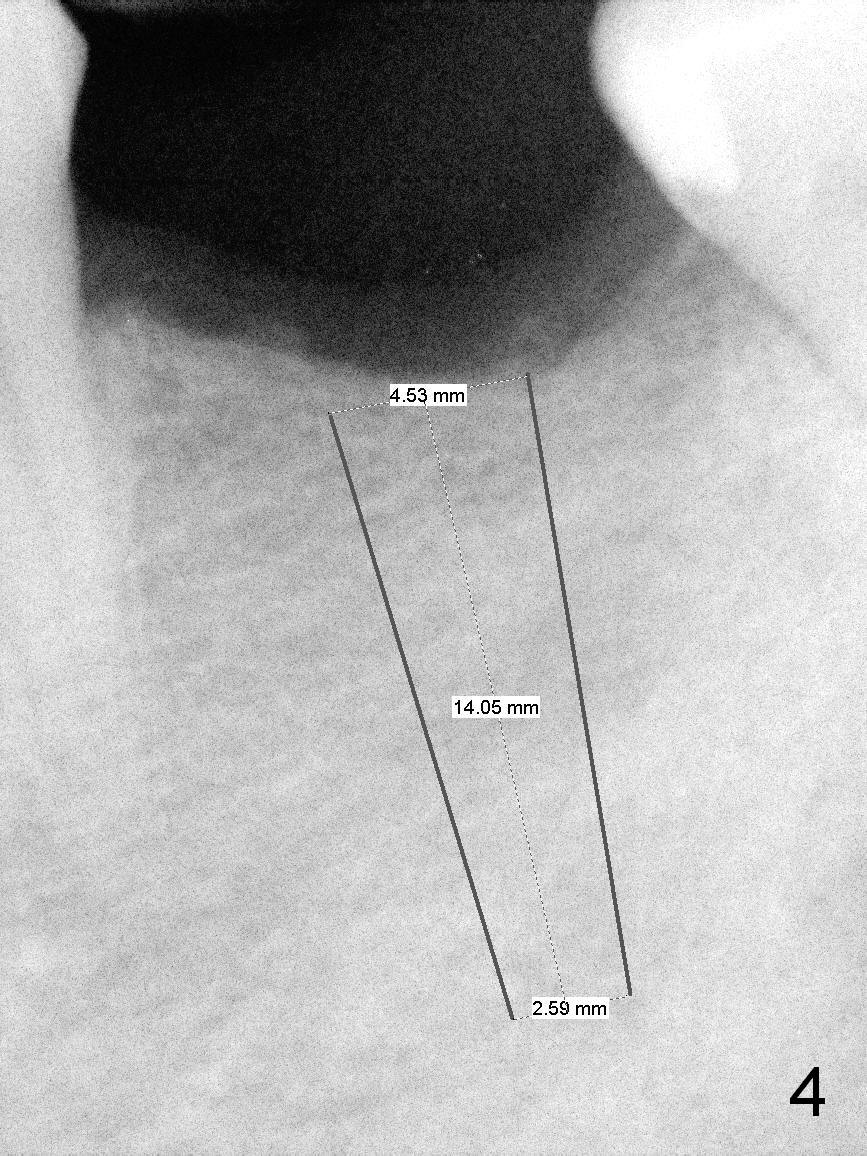

A 60-year-old man has lost the tooth #19 for approximate 20 years (Fig.1). The superior border of the Inferior Alveolar Canal is not distinct in PA. An implant that is slightly longer than the root of the neighboring tooth should be safe (Fig.2). Panoramic X-ray reveals plenty of bone height (Fig.3). Therefore, initial osteotomy depth will be 10 mm. Insert a parallel pin and take the 1st intraop PA for depth confirmation. If there is enough bone to place a 14 mm implant (Fig.4), but the crestal width is insufficient, place a 12 mm implant subcrestally to prevent thread exposure.